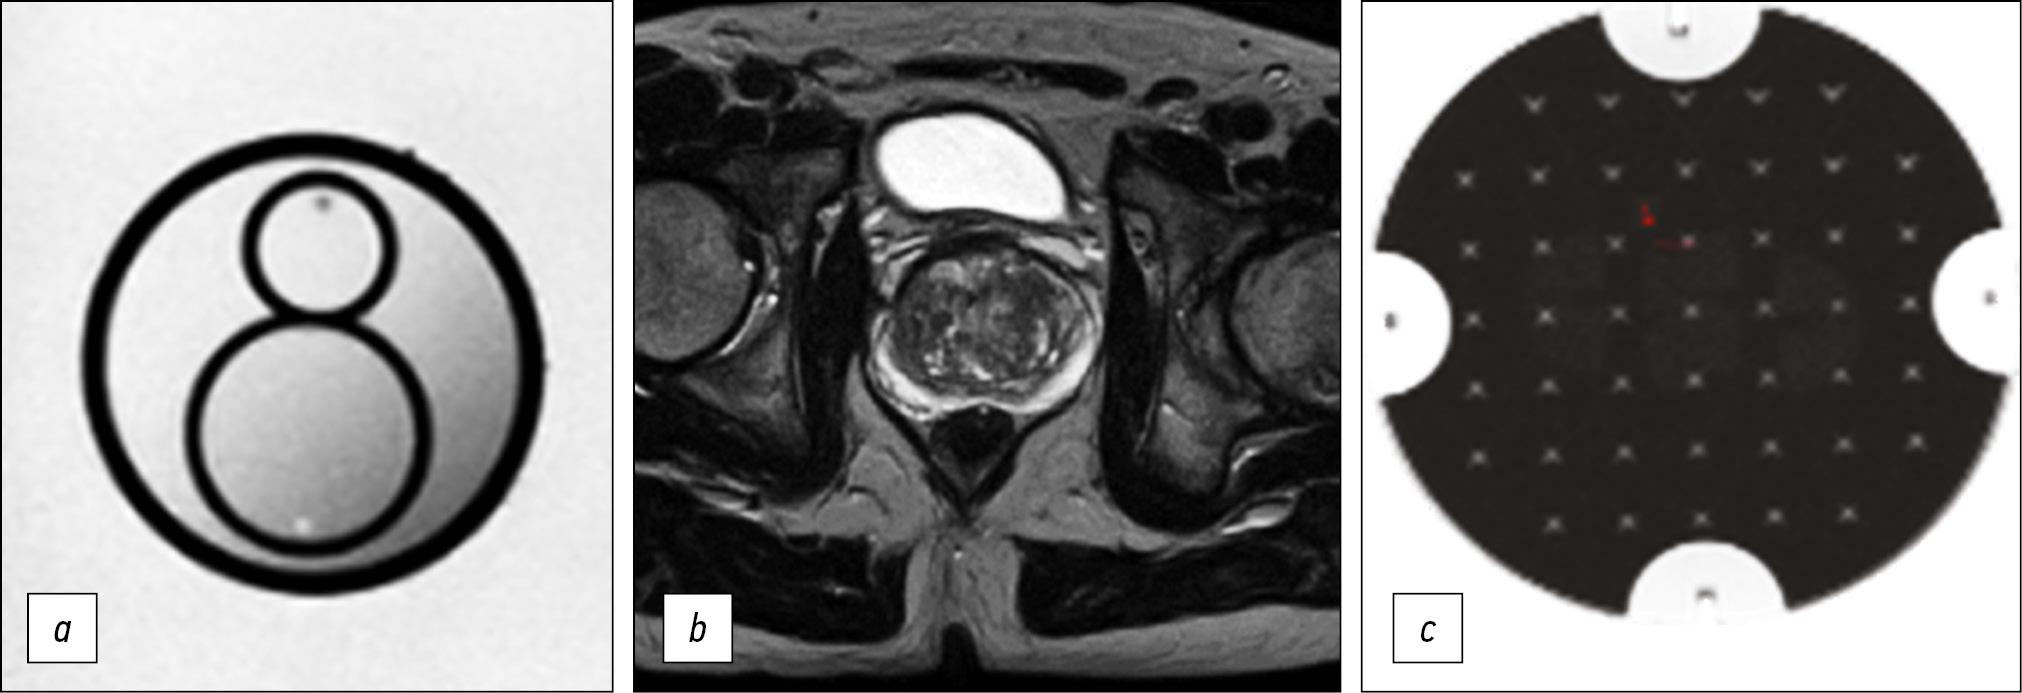

Optimized biparametric magnetic resonance imaging protocol for prostate cancer detection

MATERIALS AND METHODS: Preliminary analysis of prostate magnetic resonance imaging scanning in medical organizations of the Moscow Health Care Department showed the absence of a unified approach. Using the iterative adjustment of scanning parameters, we adjusted the protocol to ensure acceptable quality with maximum available compliance with PI-RADS v2.1.

To quantify the quality of the images, we used the magnetic resonance imaging phantom recommended by the American College of Radiology.

RESULTS: The biparametric protocol was developed for Excelart Vantage 1.5 T, including T2-weighted images in three planes and diffusion-weighted images, which took less than 11 min. Moreover, the image quality parameters (intensity inhomogeneity, nonlinearity, resolution, and slice thickness) were within the acceptable ranges recommended by the magnetic resonance imaging manufacturer.